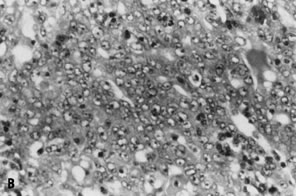

The specific cytomorphologic features of lesions in a variety of body sites will follow; however, general cytomorphologic criteria of malignancy for epithelial lesions are presented here. The most useful diagnostic criterion applied to FNA specimens is cellularity, as nearly all neoplasms (particularly malignancies) yield cellular specimens on aspiration, whereas aspirates of nonneoplastic lesions and some benign neoplasms are hypocellular. Another useful diagnostic criterion is that of architectural complexity within intact tissue fragments. Although the practice of cytology is generally thought to rely entirely on evaluation of subtle cellular and nuclear details, large tissue fragments are often present in FNA biopsy specimens of epithelial lesions and contain valuable information. In general, normal parenchyma and benign epithelial lesions are characterized by architecturally “flat,” two-dimensional fragments with well-organized and uniformly spaced nuclei (Fig. 2A), whereas malignant epithelial neoplasms generally yield complex, three-dimensional fragments with significant nuclear overlap and disorganization (Fig. 2B). Obviously, all cases must be evaluated for conventional nuclear criteria of malignancy, including variation in nuclear size, shape, and chromatin pattern in adjacent cells. In addition, nuclear membrane abnormalities, altered chromatin distribution (including both hypochromasia and hyperchromasia), and elevated nucleus-to-cytoplasm ratios are important features of malignancy in individual cells (Fig. 3).22 General cytologic features of commonly encountered lesions in the breast, lymph nodes, gynecologic tract, and pelvis will be presented.

Fig. 2. ( A) Well-organized, 2D tissue fragment typical of benign glandular epithelium (stain, Papanicolaou) in contrast to ( B) architecturally crowded, 3D tissue fragment from case of adenocarcinoma showing complete loss of cellular polarization and organization (stain, Papanicolaou).